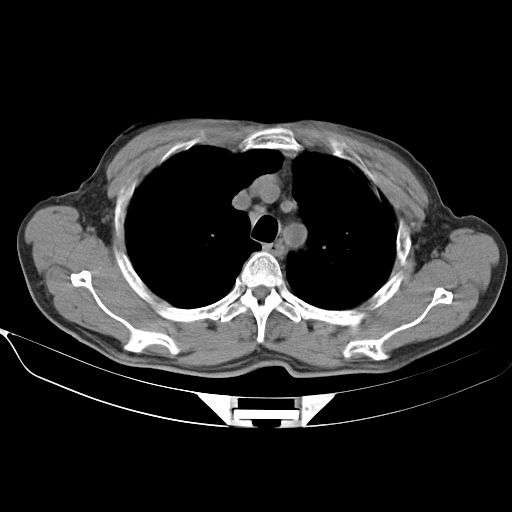

以下是引用心路寻觅在2010-3-1 10:23:00的发言:[br]1、考虑左肺上叶周围型肺癌[br]2、右上肺陈旧性病灶。[br][br][本贴已被 心路寻觅 于 2010-3-1 10:40:18 修改过]

以下是引用shuiyuan在2010-3-1 10:45:00的发言:[br]考虑左肺上叶中心型肺癌伴阻塞型炎症,邻近胸膜受侵。